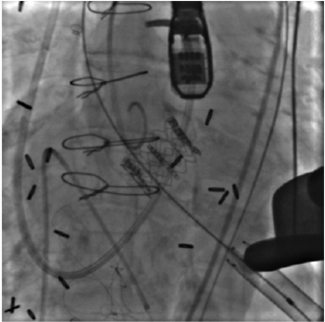

LAA Closure

03/03/2024

Akhil Mogalapalli, MD; Sundeep Kumar, MD; Tabitha Lobo, MD; Joseph Reed, MD; Luis Augusto Palma Dallan, MD, PhD; Sung-Han Yoon, MD; Steven J. Filby, MD

Reprinted with permission from J INVASIVE CARDIOL 2023;35(1):E1-E6.

In this study, the authors review their experience with the Watchman Legacy and Watchman FLX devices (Boston Scientific) and their complications at a large academic hospital in a cohort of 369 patients.